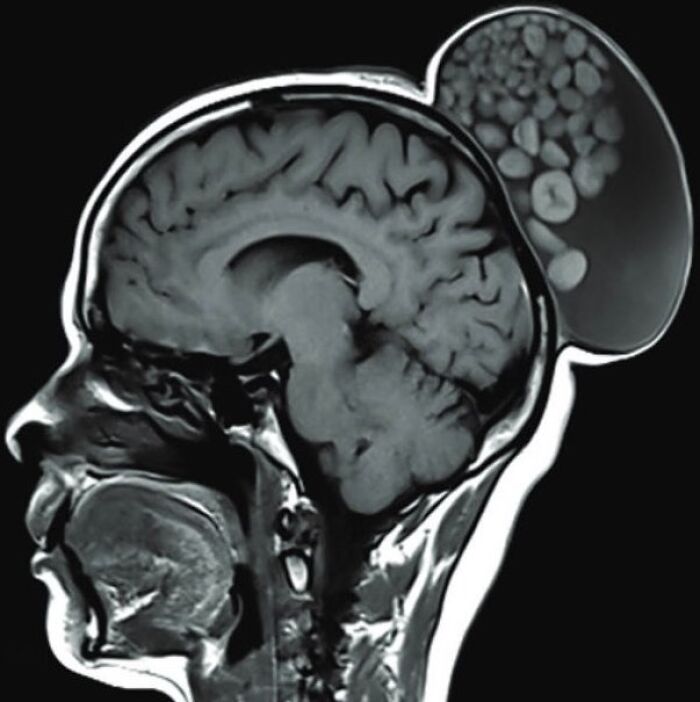

#29

52-year-old woman presented with a painless, gradually enlarging scalp swelling

#54

Bobble-head doll syndrome in an infant with an arachnoid cyst

Bobble-head doll syndrome is a rare neurological movement disorder in which patients, usually children around age 3, begin to bob their head and shoulders forward and back, or sometimes side-to-side, involuntarily, in a manner reminiscent of a bobble head doll. The syndrome is related to cystic lesions and swelling of the third ventricle in the brain. Symptoms of bobble-head doll syndrome are diverse but can be grouped into two categories: physical and neurological. The most common form of treatment is surgical implanting of a shunt to relieve the swelling of the brain.

A 1.5-year-old girl presented to the pediatric clinic with the chief complaints of gradual onset excessive head nodding (side-to-side movement) for 3 months. Movements increased with walking, emotions, and stress; decreased during periods of concentration; and were absent during sleep. There were no other complaints or headaches. There was no other significant history.

The child was alert, with normal cognitive function. Neurological examination was normal. Initial laboratory assessment including CBC, hepatic and renal function, and endocrine function tests were normal.

Cranial MRI demonstrated a large left-hemispheric cystic process with a midline shift, well-defined thin-walled suprasellar arachnoid cyst measuring 3 × 5 × 7 cm that obstructed the foramina of Monro, with resulting hydrocephalus ventriculomegaly. Based on the cranial MRI and symptoms, a diagnosis of a suprasellar arachnoid cyst with BHDS was made. The patient underwent endoscopic cystoventriculostomy and cystocisternostomy for the suprasellar arachnoid cyst. During the 6 months of follow-up, the head bobbing disappeared completely, and her growth was normal.

Despite the rareness of bobble-head doll syndrome, it is considered an important condition that must be investigated early to detect the cause and treated promptly to avoid potential complications.